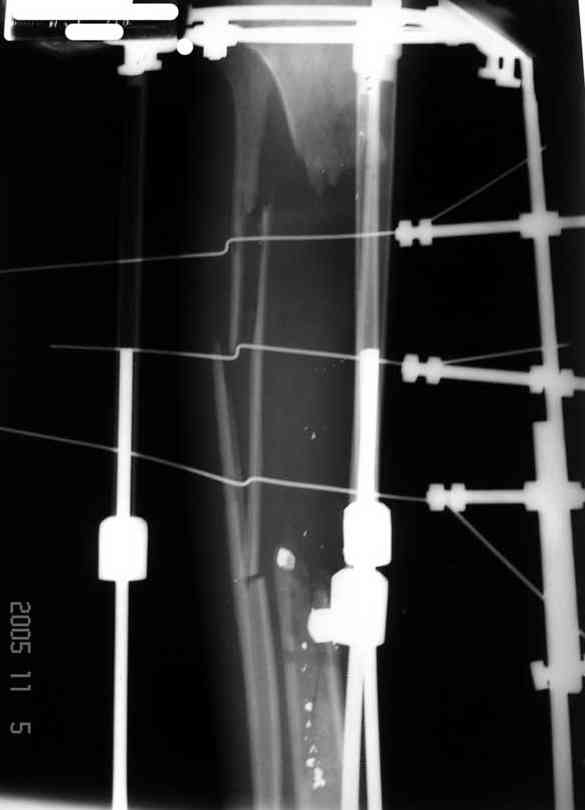

Илизарова (как придется), хирургически обработали и героически заживляли мягкие ткани с многочисленными кожными пластиками. В итоге через полгода я принял его вот таким:

Реализовал описанную выше методику, и в итоге вот что получилось. Высылаю лишь прямые проекции,

в боковых тоже всё в тему.

Очень пригодились карбоновые кольца (Джолдас -огромное спасибо, я твой должник!!!), поскольку остеопороз дистального отломка был просто невероятный. На цифровом рентгене с трудом угадывались контуры.

Рентген в процессе перемещения - внизу карбоновые кольца, тракция фрагмента спицами с упором.